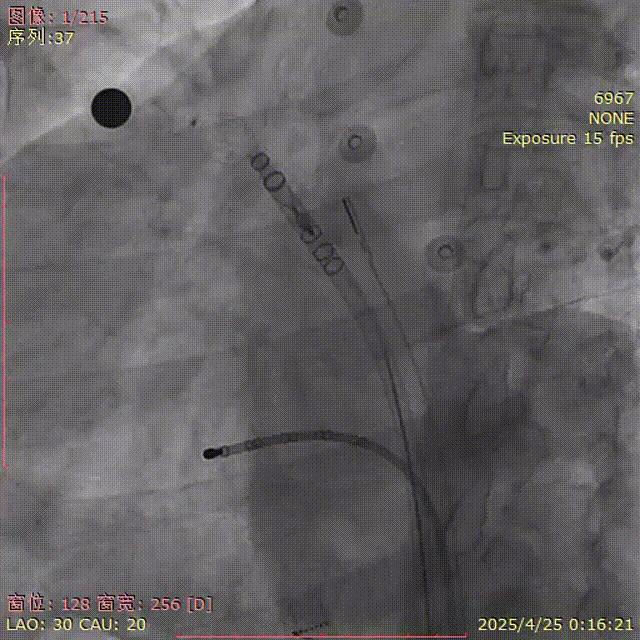

初次展开

由于上叶空间狭小,调整鞘管过程中猪尾滑落至下分叶,尝试在下分叶处展开封堵器,轴向欠佳。

下分叶空间狭窄,封堵器远端被挤出,下缘露肩过多,考虑重新走上叶放置。

展开后造影

封堵器呈热狗型,下缘轻微露肩